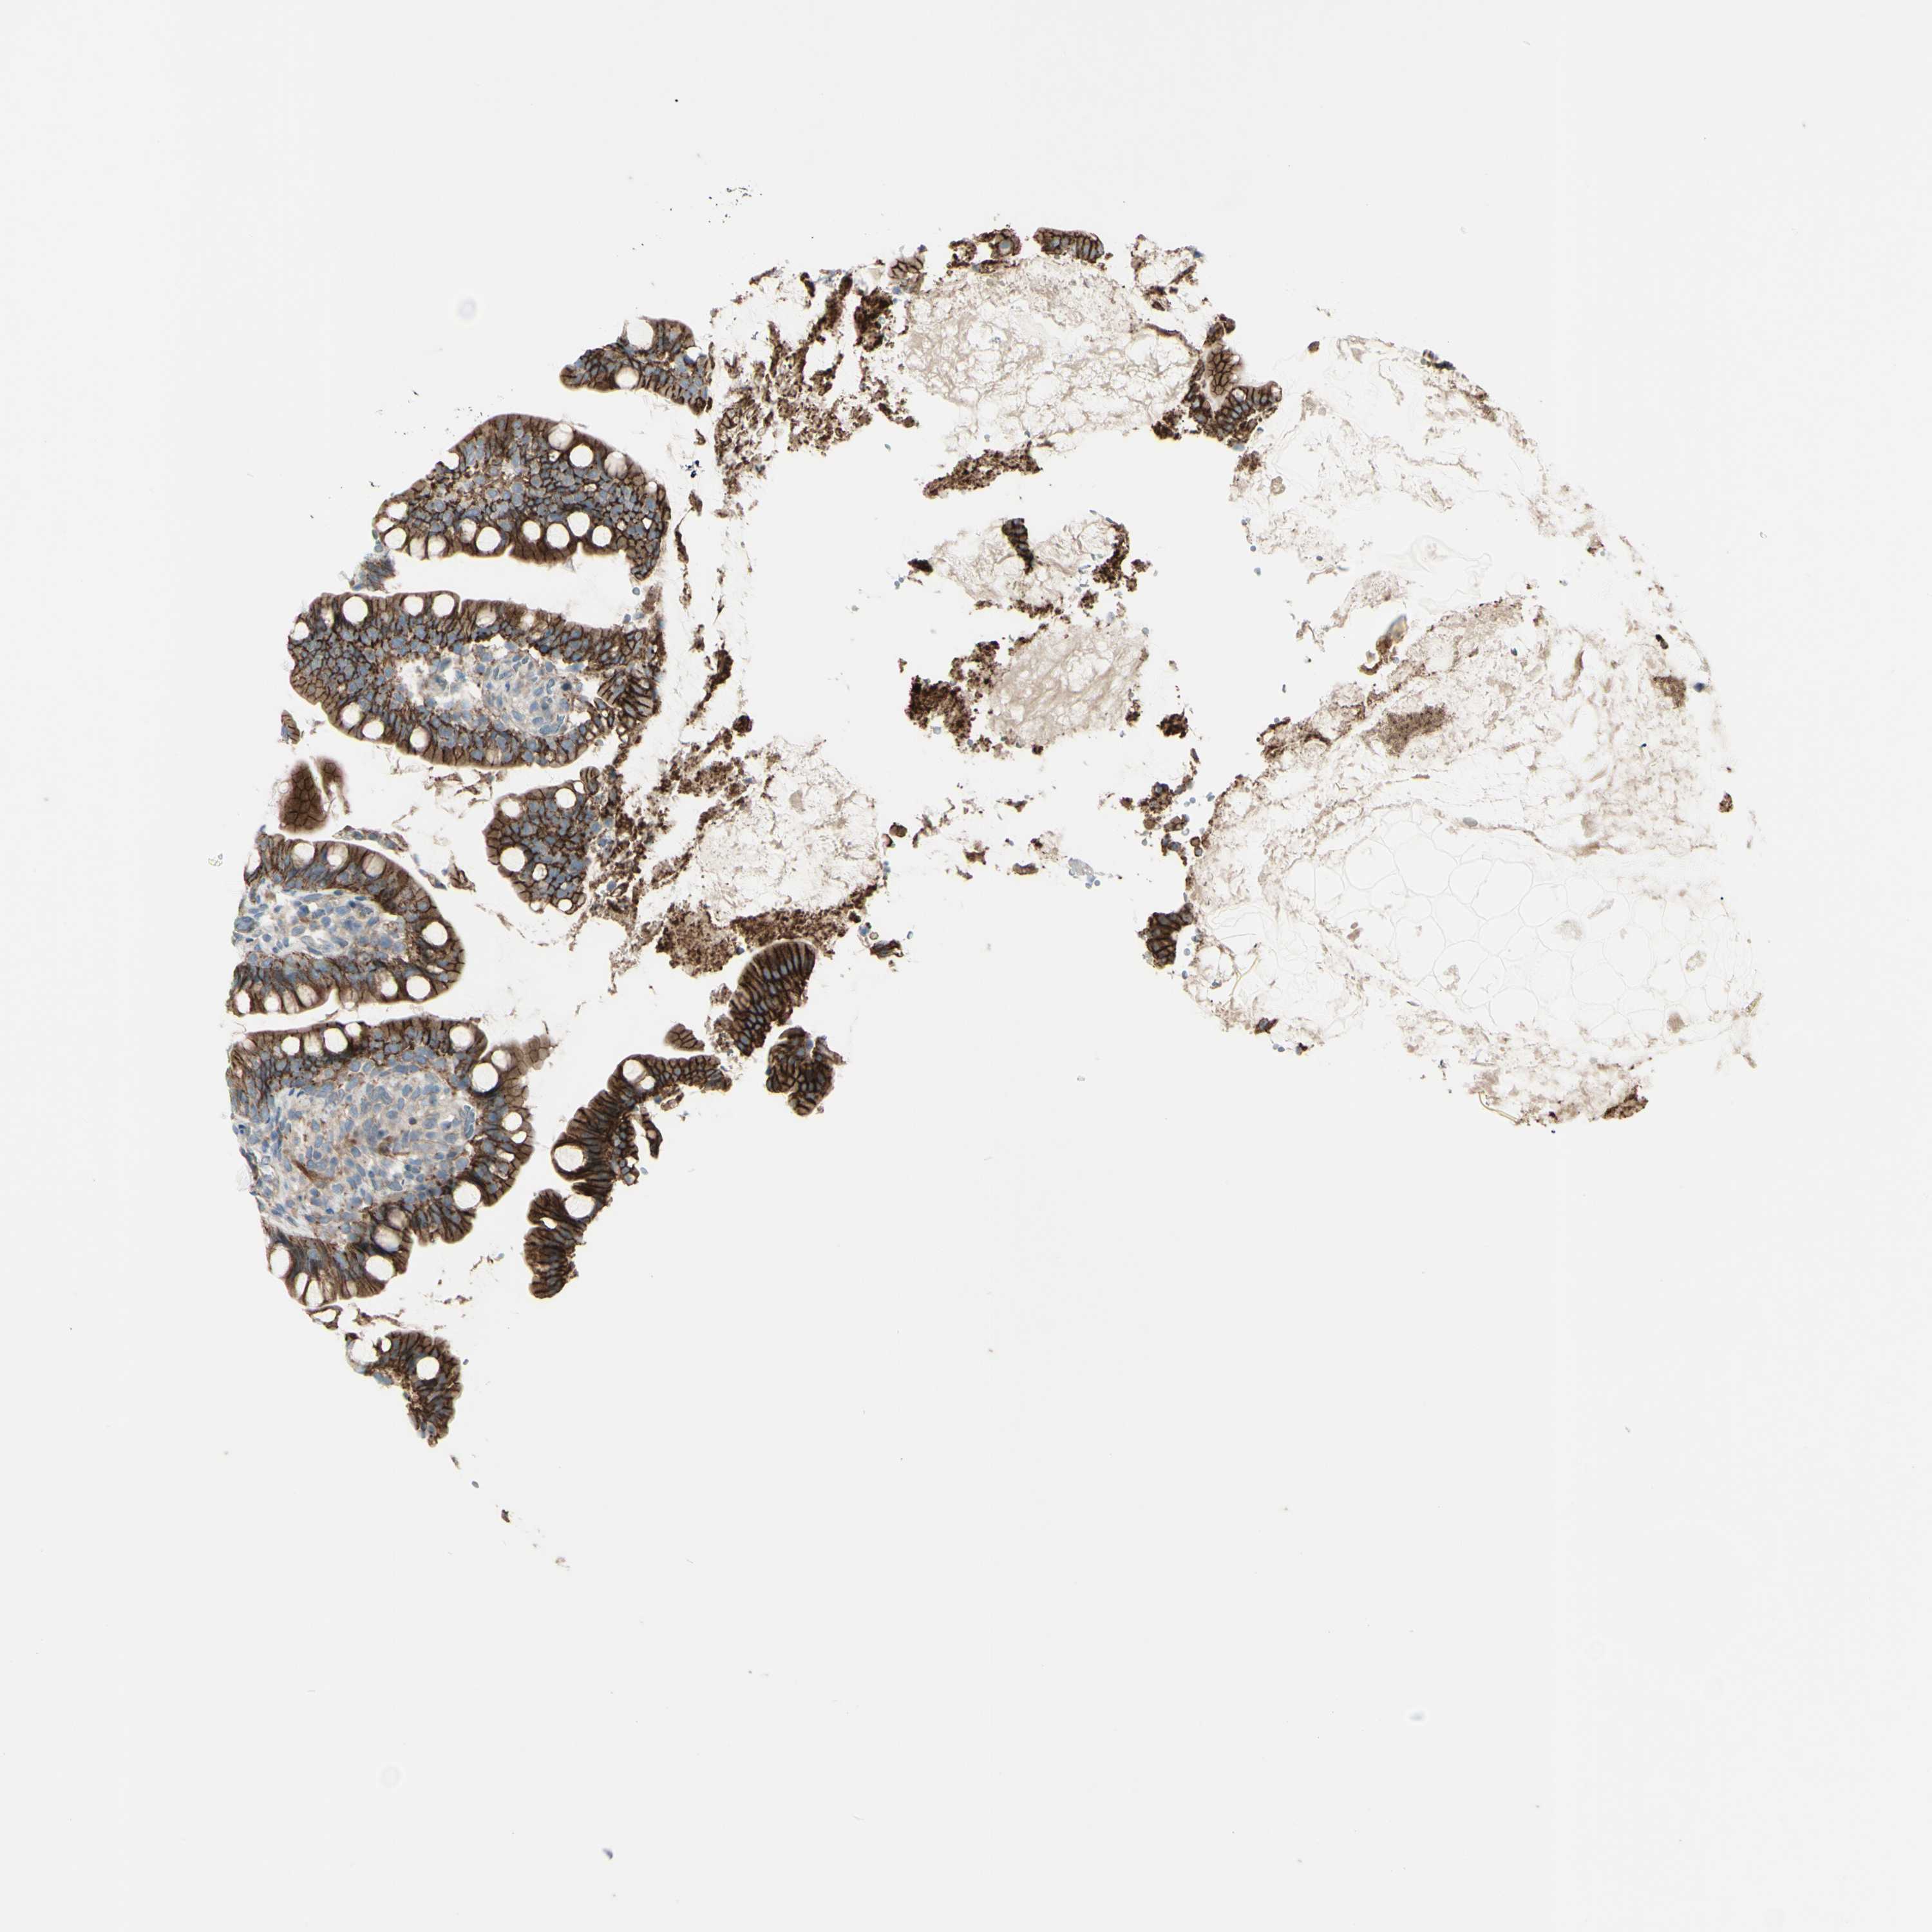

SMALL INTESTINE - Antibody stainingi

Antibody staining in the annotated cell types in the current human tissue is reported as not detected, low, medium, or high, based on conventional immunohistochemistry profiling in selected tissues. This score is based on the combination of the staining intensity and fraction of stained cells.

Each image is clickable and will lead to virtual microscopy that enables deeper exploration of all samples and also displays staining intensity scores, fraction scores and subcellular localization as well as patient and tissue information for each sample.

Antibody HPA010537

Glandular cells High